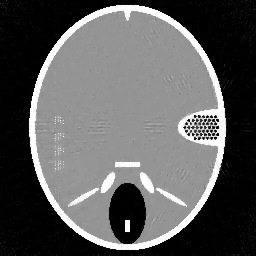

Figure 1. Phantoms for tests. (a) Head phantom used for simulation [24], (b) gel phantom used for real X-ray scan.

For the experiments, we test our method on a simulated head phantom from [24] and a real gel phantom shown in Figure 1. Here, we consider a 2D CT scenario. The detector has full coverage of the object at any projection angle, and a constant angular spacing of the rays is set in the interval of [0,π]0𝜋[0,\pi].

Example 1. Our first test example is on the simulated head phantom, which is generated in a square domain of 256×256256256256\times 256 pixels, i.e., there are 2562=65,536superscript256265536256^{2}=65,536 unknowns. With 362 beams and 45 projection angles, the correspond CT reconstruction problem has an under-determined rate of 25%. The measurements are given by f=Au¯+ϵ𝑓𝐴¯𝑢italic-ϵf=A\bar{u}+\epsilon, where u¯¯𝑢\bar{u} is the ground truth (the true attenuation coefficients in the object) and ϵitalic-ϵ\epsilon denotes the additive white Gaussian noise with the noise level ϵ/Au¯normitalic-ϵnorm𝐴¯𝑢\|\epsilon\|/\|A\bar{u}\|.

In order to study the behaviour of our method, we compare it with the filtered back-projection (FBP) algorithm [15], the Landweber method [15], the Kaczmarz’s method [8], and the L2-TV reconstruction method, which solves the variational model (1) with TV regularization as proposed in [19]. All methods are solved under a non-negativity constraint. Note that in the L2-TV method the regularization parameter α𝛼\alpha is scalar, which is chosen to give the largest signal-to-noise ratio (SNR).

In Figure 2 and 3, we give the reconstruction results, which are shown in the same intensity range as the original phantom, from the simulated measurements with the noise level 0.2 and 0.8, respectively. Since the FBP algorithm is according to the analytical formulation of the inverse X-ray transform, it implicitly requires to have continuously measured clean data from the whole 0 to π𝜋\pi angular range. Therefore, it is not suited for reconstructing from noisy limited data. We can clearly see many stripe artifacts due to the noise and sparse projection angles in the FBP results. Both the Landweber and Kaczmarz’s methods perform better than FBP, but there are still some visible artifacts in the reconstruction. By using the TV regularization in the L2-TV and our methods, we potentially assume that the reconstructions are piecewise constant, which evidently reduces the influence of the noise and avoids stripe artifacts. In addition, comparing the results from the L2-TV and our methods, we find that our method suppresses artifacts much better while reconstructing most details. For instance, the grey region in the head and the black dotted region on the right side. With respect to SNR, it is also clear that our method gives the best reconstruction results. In Figure 2 (f) and Figure 3(f), we also plot the λ𝜆\lambda function obtained by our method. One can see that in the more textured regions λ𝜆\lambda is large in order to preserve the details, and in the more homogenous regions it is small to reduce artifacts.